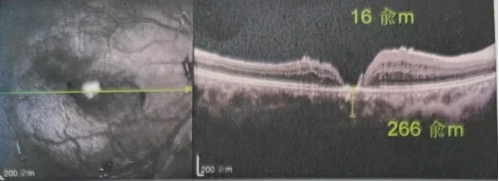

由于自身患有頸椎病,每次術(shù)后長(zhǎng)期的趴睡都讓他痛苦不堪。為了尋求更好的治療,吳爺爺來(lái)到廈門(mén)大學(xué)附屬?gòu)B門(mén)眼科中心,找到了眼外傷及眼底病2科的李海波博士后。此時(shí),吳爺爺右眼的黃斑裂孔已經(jīng)持續(xù)擴(kuò)大到780μm,演變?yōu)殡y治性的大裂孔。

最讓吳爺爺難以置信的是:術(shù)后只需保持平躺24小時(shí)!第二天復(fù)查時(shí),眼底鏡及OCT檢查清晰顯示——那個(gè)折磨了他大半年的大裂孔,竟然閉合了!且吳爺爺?shù)挠已垡暳τ辛嗣黠@的改善,術(shù)后3天已經(jīng)可以看到 0.15。